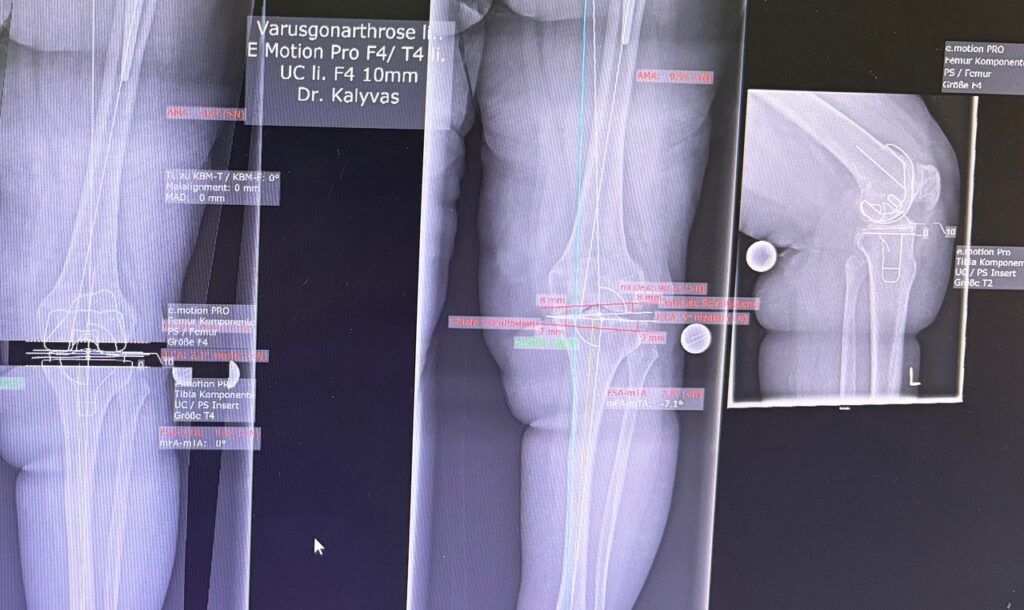

Η ρομποτική αρθροπλαστική γόνατος είναι προηγμένη τεχνική αντικατάστασης γόνατος, όπου ο χειρουργός χρησιμοποιεί ρομποτικό σύστημα υποβοήθησης για εξαιρετικά ακριβή τοποθέτηση των εμφυτευμάτων, βασισμένη στη δική σου ανατομία.

- Προεγχειρητικός σχεδιασμός με CT (συνήθως) → 3D μοντέλο γόνατος

- Καθορισμός ακριβών ορίων κοπών και ευθυγράμμισης

- Το εμφύτευμα τοποθετείται με χιλιοστομετρική ακρίβεια

Η τελική επιλογή της χειρουργικής τεχνικής γίνεται μετά από αναλυτική κλινική αξιολόγηση και προσεκτικό προεγχειρητικό σχεδιασμό, με στόχο το βέλτιστο και ασφαλέστερο αποτέλεσμα για τον ασθενή. Απαραίτητη προϋπόθεση για την επίτευξη εξαιρετικών αποτελεσμάτων αποτελεί η εξειδίκευση του χειρουργού στη συγκεκριμένη τεχνική, καθώς και η εκτεταμένη εμπειρία με μεγάλο αριθμό επεμβάσεων. Ο έμπειρος ορθοπαιδικός χειρουργός κ. Νικόλαος Καλύβας εφαρμόζει την ρομποτική τεχνική σε μεγάλο αριθμό χειρουργείων.

- Γίνεται προεγχειρητική απεικόνιση (συχνά MRI ή CT), δημιουργείται 3D πλάνο και κατασκευάζονται εξατομικευμένοι οδηγοί(jigs) που “κουμπώνουν” στο οστό και καθοδηγούν τις κοπές.